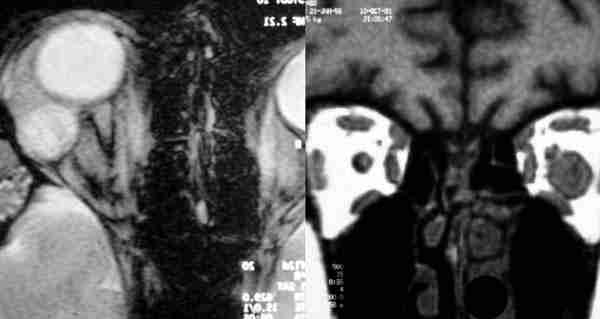

Figura 24. La resonancia nuclear magnética delimita claramente el

angioma cavernoso intraconal.

El TC y la RNM delimitan la extensión y características de la invasión de

canal óptico y quiasma, teniendo la RNM más definición.